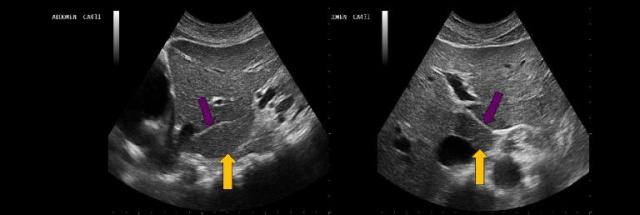

What structure is indicated by the yellow arrow?

Main lobar fissure

The yellow arrow on the image represents which of the following structures?

Caudate lobe

The purple arrows point to which of the following liver structures?

Ligamentum teres

the purple arrow on the images represents, which of the following structures?

Ligamentum venosum